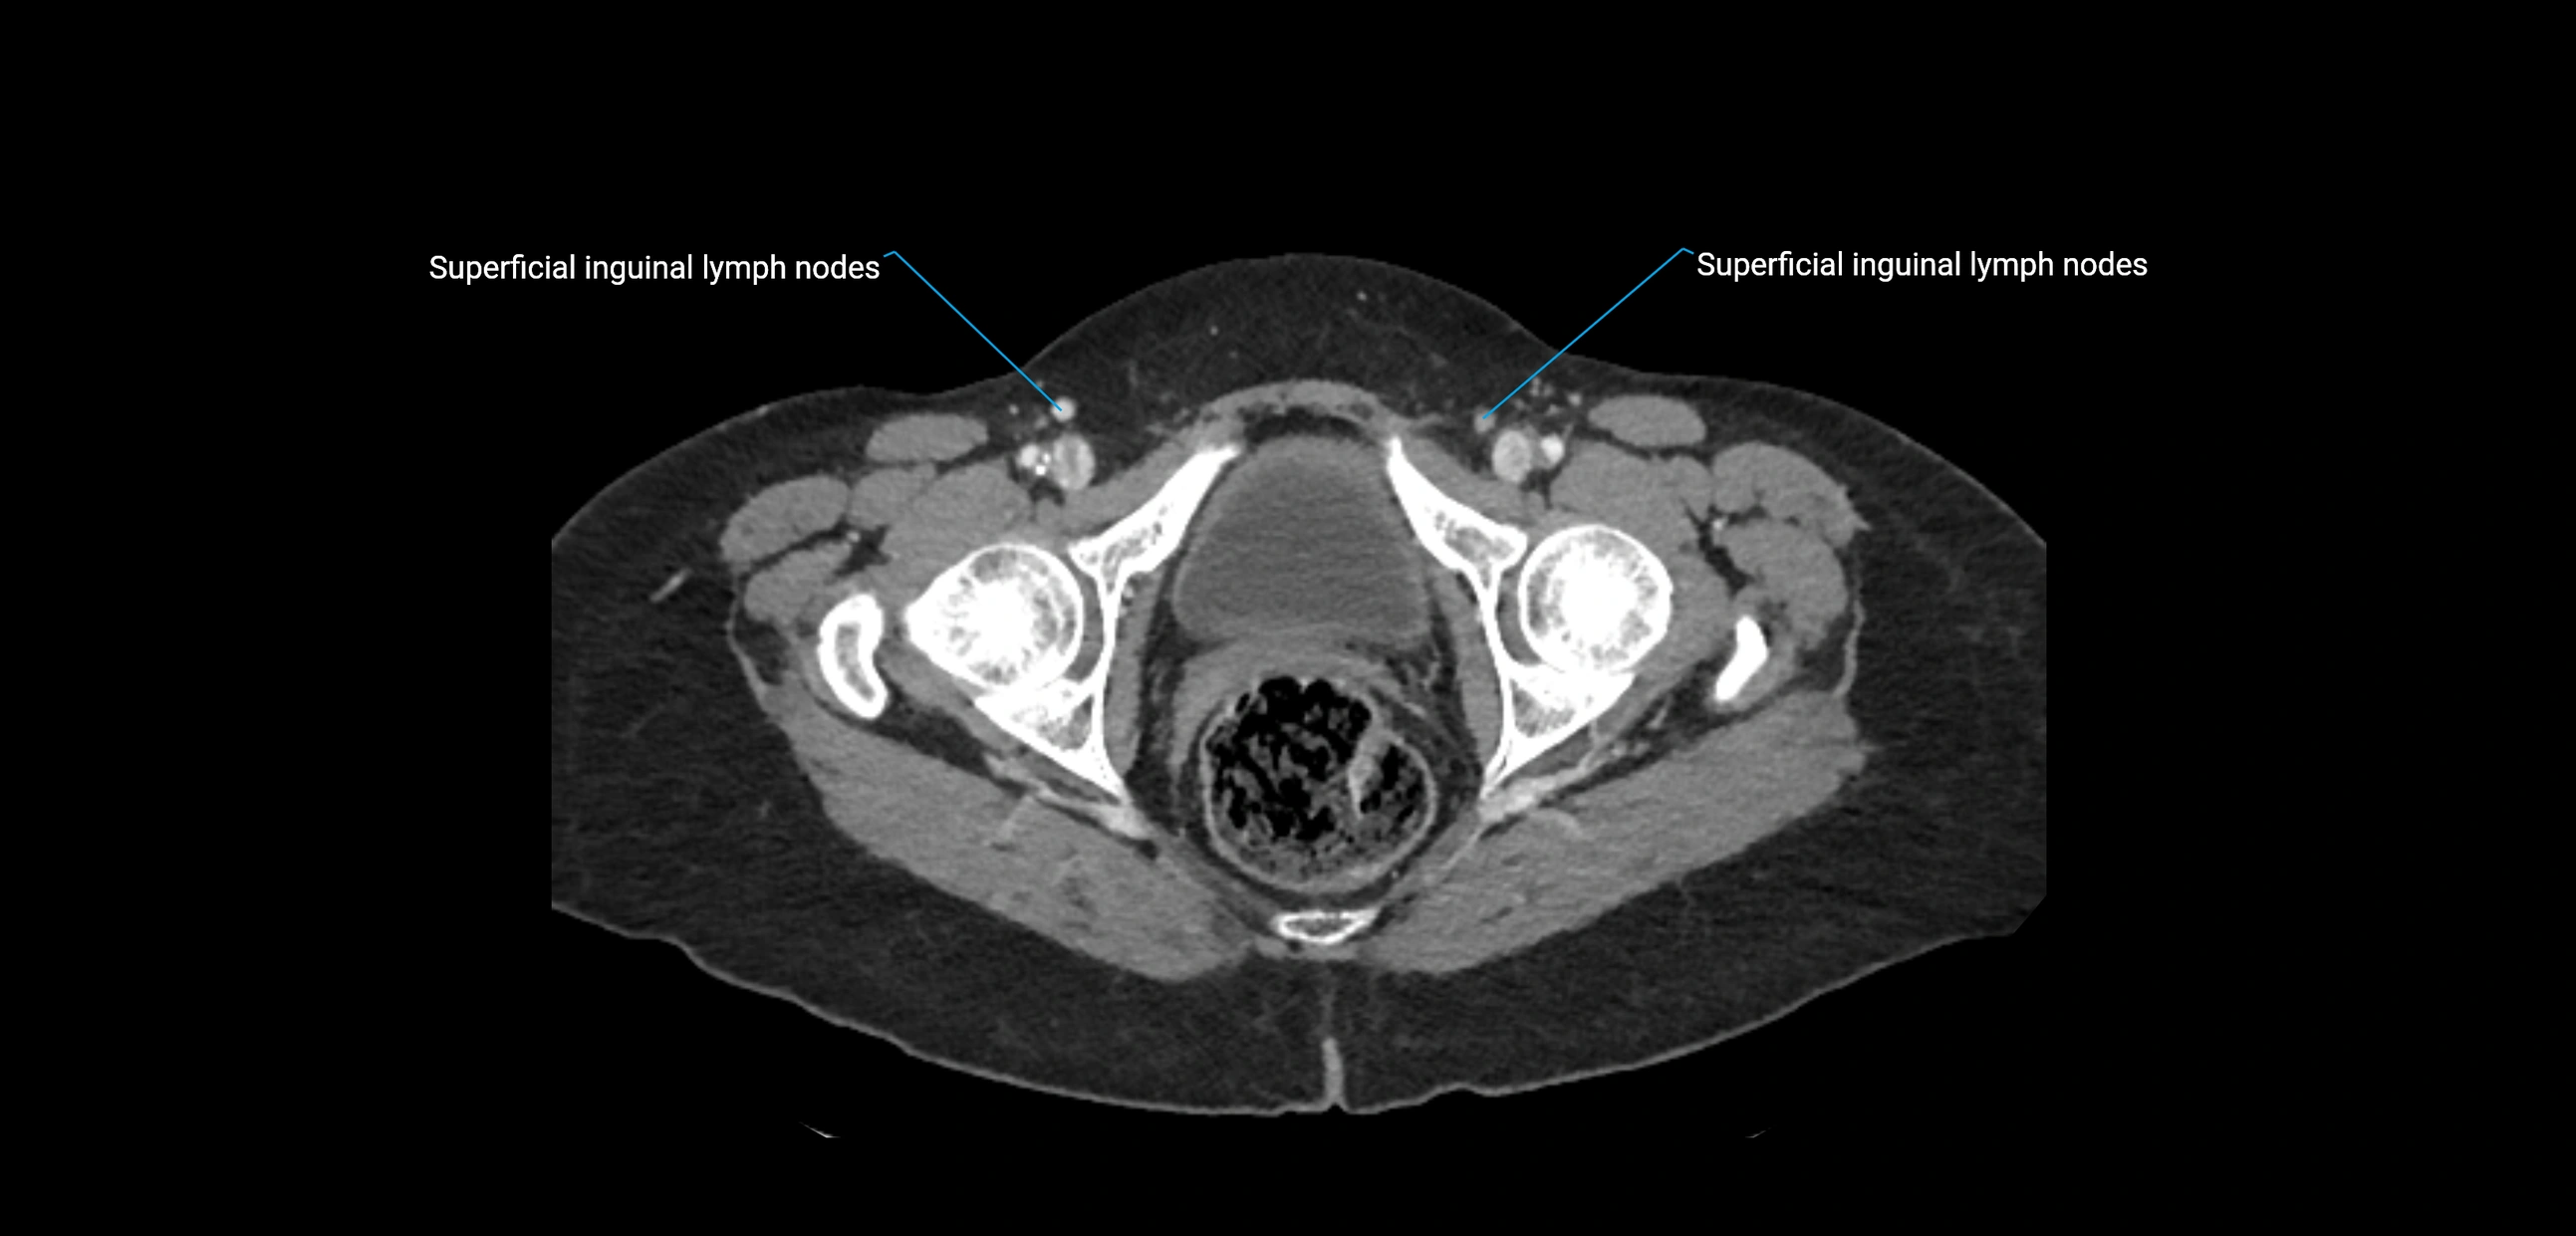

CT Appearance

CT Pre-Contrast:

• Nodes appear as soft-tissue density nodules adjacent to the aorta and IVC

• Calcification may be seen in chronic infections (e.g., tuberculosis)

CT Post-Contrast:

• Normal nodes enhance homogeneously

• Malignant nodes may show heterogeneous enhancement, central necrosis, or conglomerate formation

• Size >1 cm short axis is suspicious, though morphology and distribution are equally important